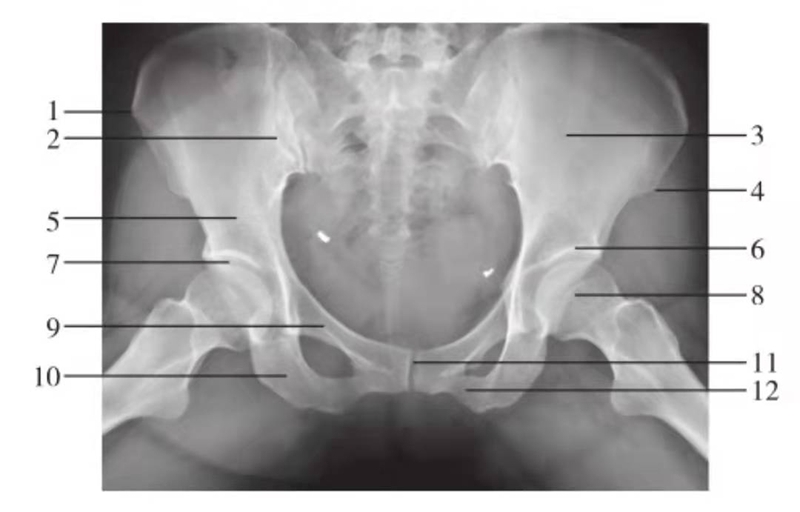

骨盆前后位

图6 骨盆正位

1.髂骨翼;2.骶髂关节;3.髂前下棘;4.髂骨体;5.髋臼顶;6.股骨头凹;7.股骨头;8.股骨颈;9.耻骨上支;10.大转子;11.坐骨支;12.耻骨联合;13.耻骨下支;14.小转子